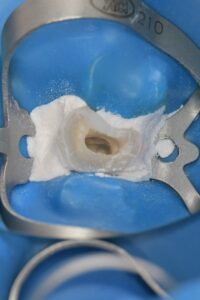

そこでこの細菌を治療中に入れないようにラバーダムというゴムのシートをかけ治療をすることで成功率を上げていきます。

↑がラバーダムをしている写真になりますが、ラバー自体も汚れているため術野の消毒を行わないといけません。

ラバーダムに高濃度の過酸化水素とポピドンヨードを用いて消毒を行い無菌的な環境が完成となります。